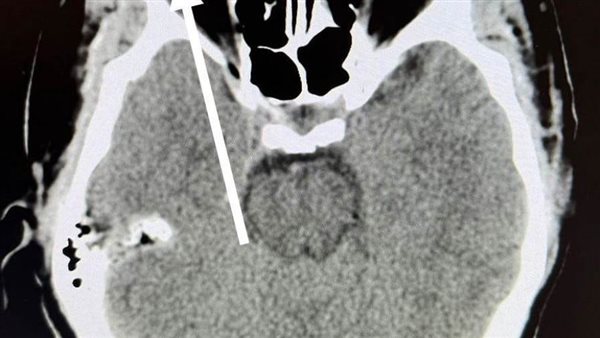

ومن جانبه، أوضح الدكتور مجدي القاضي عميد كلية الطب البشري، أن قسم الطوارئ بالمستشفي الجامعي استقبل "عامل" يعمل في تقطيع الحديد بالصاروخ بدون استخدام اي وسائل حماية مما أدي الي دخول "شظية" اخترقت جميع طبقات العين وتسببت في تهتك في القرنية والعدسة والجسم الزجاجي لتستقر في الشبكية، مشيراً الي ان المستشفى الجامعي تعد القبلة الاولى التي يقصدها جميع حالات الطوارئ من كل الجهات وعلى مدار ٢٤ ساعة بالمجان علي نفقة الدولة او الخاضعين لمظلة التأمين الصحي.

ومن جانبه قال الدكتور محمود فاروق استاذ الشبكية، أن الفريق المعالج نجح إجراء عملية دقيقة اسفرت عن استئصال الجسم الزجاجي، و الوصول الي قاع العين لإزالة الجسم الغريب وعمل كي للشبكية "بالليزر" لتجنب حدوث انفصال شبكي وتم إنقاذ عين المريض من العمي المحقق.